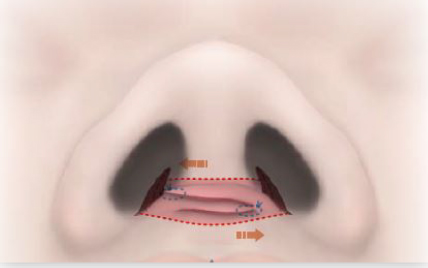

鼻翼(小鼻)の底部手術は、鼻翼の上部の縮小効果を得るために鼻孔底粘膜を菱形に切除します。

切除デザインを調節することで縮小効果だけでなく、鼻翼のカーブの形や鼻翼挙上効果を得ることも可能です。